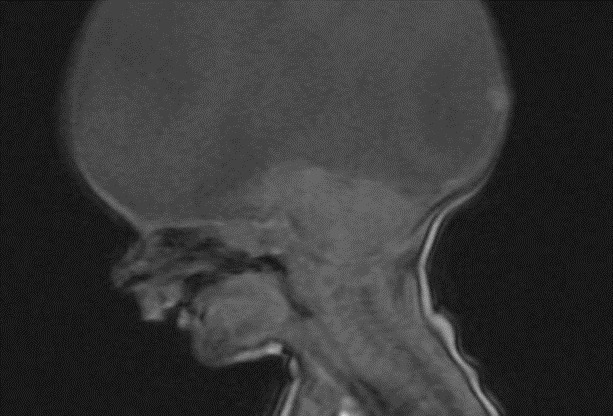

图片均来自网络男孩生下来就没有大脑,医生劝诫放弃,可男孩的父母却让事情发生了扭转!而他的父母也诠释了什么叫做“生命的坚强”!在荷兰,一对夫妇生下了一位天生无脑男孩,这样的噩耗确实给这对夫妇带来了承重的打击和心痛!

在男孩2岁的时候,夫妇俩发现男孩根本不能动也不能讲话,便将男孩带去医院检查!检查结果显示,男孩依旧还是无脑孩子,医生告诉夫妇俩,他们的儿子每日的存活是没有大脑意识的,就像是行尸走肉,医生劝解夫妇俩让男孩安乐死!